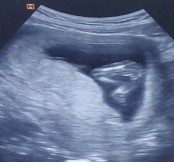

ในรูปอัลตร้าซาวด์ หญิงหรือชายคะแม่ๆ 14 w5วันคะหรือว่ายังเล็กอยู่#คุณแม่ๆช่วยแนะนำหน่อยค่ะ

ถ้าไม่มีติ่งงอกออกมา ต่อให้เล็กแค่ไหนก็ยังมองเห็นค่ะ อันนี้เรียบ ผู้หญิงค่ะ ส่วนตัวบ้านนี้เห็นตอน 16 สัปดาห์เหมือนกัน อ้าขาแบบนี้เหมือนกันค่ะ

ยังเล็กอยู่ค่ะ แต่น่าจะไปทางหญิง รอสัก 20W อวัยวะจะเห็นชัดกว่านี้ค่ะ